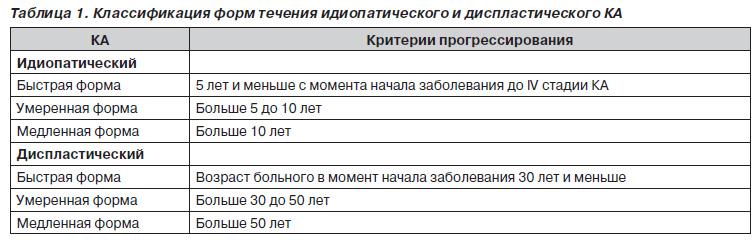

Обследованы образцы хрящевой ткани с головок бедренных костей, удаленных интраоперационно при выполнении эндопротезирования, больных с идиопатическим и диспластическим КА IV стадии по J.H. Kellgren и J.S. Lawrence [17]. Для определения форм прогрессирования КА использовали классификацию течения патологического процесса [3], которая представлена в табл. 1.

Были исследованы образцы суставной хрящевой ткани с головок бедренных костей у 25 больных с быстрой, у 9 — с умеренной и у 13 — с медленной формой течения идиопатического КА и 19 образцов хрящевой ткани у больных с диспластическим коксартрозом, из них с быстрой формой течения — 7, с умеренной — 7, с медленной — 5.

Анализ полученных данных при исследовании хрящевой ткани у больных с идиопатическим коксартрозом медленной формы прогрессирования показал сниженное содержание ГАГ, в процентном отношении — 65 %, в абсолютных показателях — 2,38 ± 0,05 мкг/мг, при норме 3,64 ± ± 0,12 мкг/мг. Еще более выраженные изменения происходят в содержании ГАГ у больных с умеренной формой прогрессирования идиопатического КА — 2,02 ± 0,14 мкг/мг, при быстрой форме — 1,70 ± 0,05 мкг/мг, что составило 55 и 47 % соответственно от физиологической нормы (табл. 2, рис. 1).

Данные, полученные при исследовании хрящевой ткани у больных с коксартрозом, свидетельствуют о снижении содержания органических компонентов соединительной ткани (табл. 2, 3, рис. 1–4).

Соответствующие изменения наблюдали в хрящевой ткани больных с диспластическим КА. При медленной форме течения содержание ГАГ — 58 % относительно нормы, в абсолютных показателях — 2,13 ± 0,18 мкг/мг (норма 3,64 ± 0,12), а также выраженные изменения происходили в концентрации ГАГ у больных с умеренной формой заболевания — 1,55 ± 0,07 мкг/мг, при быстрой форме — 1,50 ± 0,11 мкг/мг, что составило 42 и 41 % соответственно (табл. 3, рис. 2).